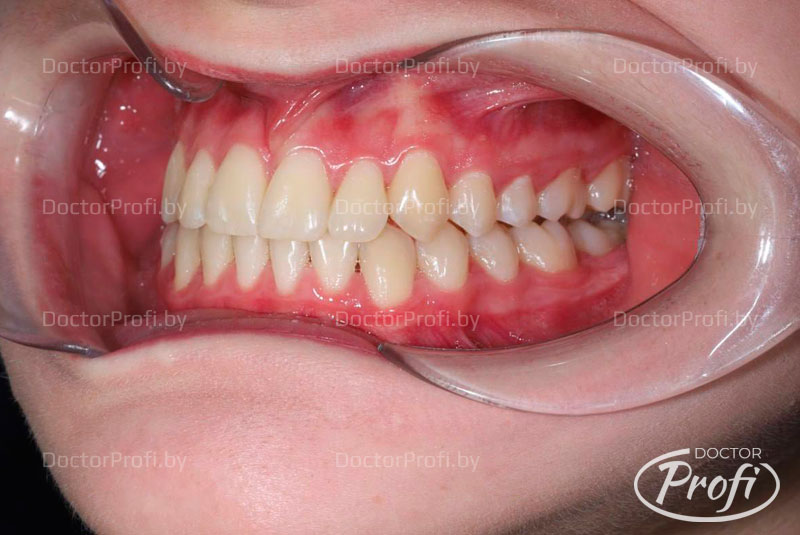

На основании полученных данных был установлен диагноз: двусторонний буккально-перекрестный прикус со смещением нижней челюсти вправо, дистальное соотношение зубов справа и тенденция к мезиальному прикусу слева; сужение и укорочение зубных дуг; скученное положение резцов на верхней и нижней челюсти с полным дефицитом места для зуба 22, а также истирание твердых тканей зуба 22 в пределах дентина; множественные ротации зубов и смещение центральной линии верхней челюсти влево на 3 мм.

Лечение проводила врач-ортодонт Дегтерева Илона Валерьевна с использованием самолигирующей брекет-системы Damon Q2 на обеих челюстях с избирательной пришлифовкой эмали на контактных поверхностях зубов во фронтальном отделе.

После снятия брекет-системы были установлены ретейнеры, а эстетическая реставрация зуба 22 была выполнена стоматологом-терапевтом высшей категории медицинского центра «Доктор Профи» Заблотской Екатериной Николаевной.

В результате проведенного лечения удалось достичь впечатляющих эстетических и функциональных результатов, что позволило пациентке обрести уверенность в своей улыбке